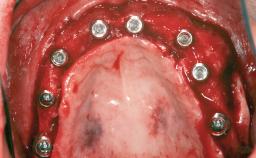

# of Implants 3

Type of Implants One-Piece

Bone Augmentation Horizontal|Staged|Vertical

Augmentation Materials Autogenous chips|Autogenous block(s)|Xenogenous